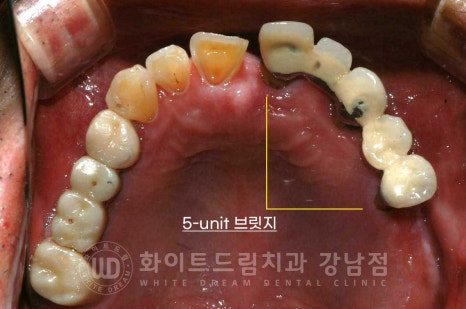

상악 브릿지 치료가 되어 있는 치아 부위는 이미 사용이 불가능할 정도로

염증이 심한 상태였고, 브릿지 통째로 빠질 것처럼 심한 흔들림을 동반하고 있었습니다.

염증이 심한 치아에 발생하는 주 증상 치아 돌출 & 치아 뿌리 노출도 확인되고

이로 인해 교합도 틀어진 상태입니다.